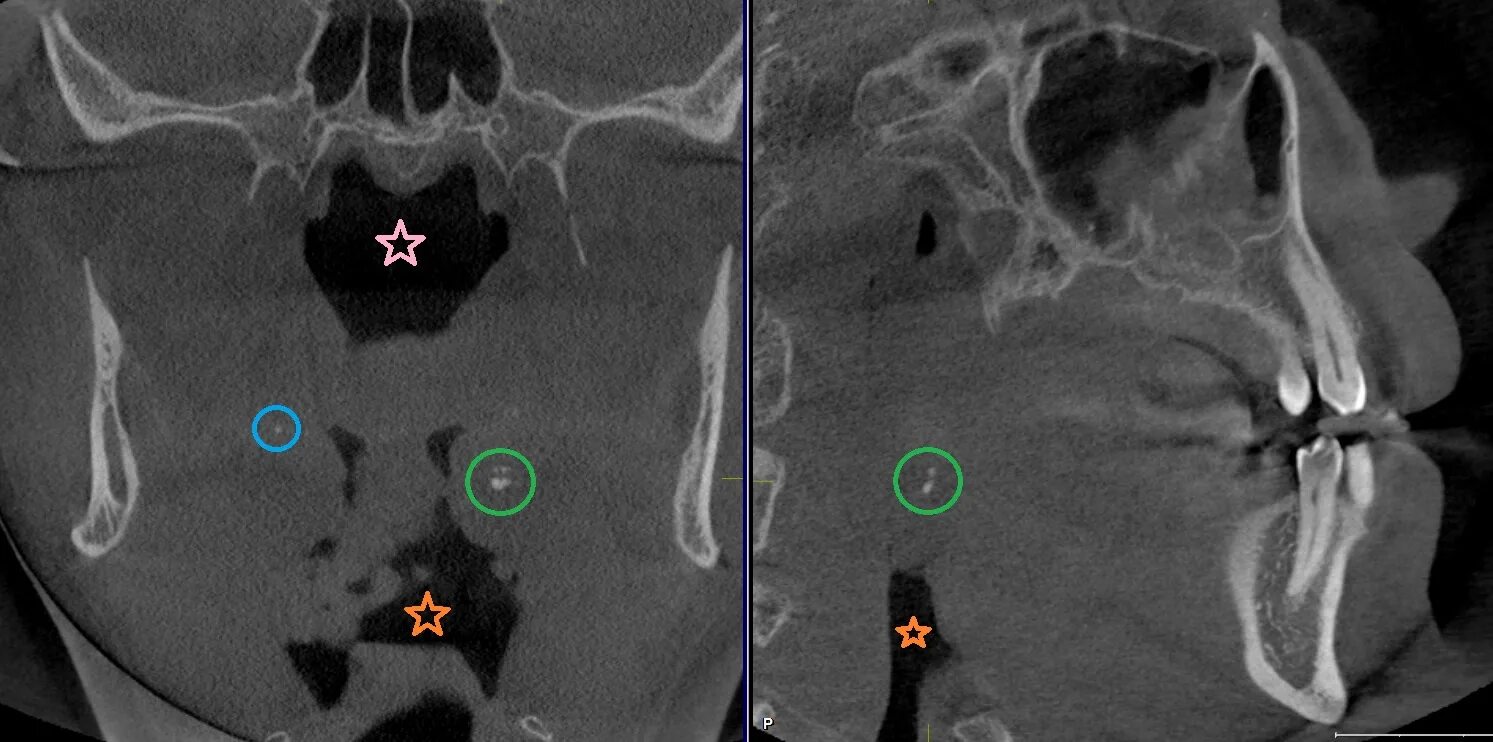

Миндалины на кт